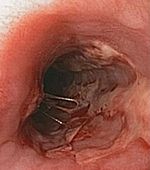

Herpes esophagitis Symptoms may include painful swallowing (odynophagia) and difficulty swallowing (dysphagia). It is often associated with impaired immune function (e.g. HIV/AIDS, immunosuppression in solid organ transplants).

Herpes esophagitis.JPG